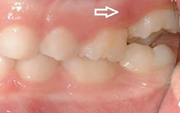

) Röntgenülesvõte. Ülemise esimese jäävmolaari lõikumine on takistatud 2. piimamolaari tõttu

Esimese jäävmolaari ektoopiline lõikumine

Ravijärgne seis. Jäävhammas on täielikult lõikunud.